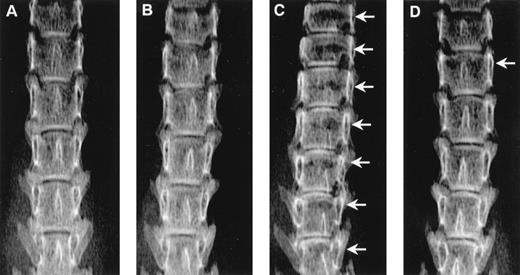

Radiographs showing the effect of ibandronate (4 μg per mouse per day for 28 days) on osteolytic lesions (arrows) in the lumbar vertebrae of 5TGM1 myeloma-bearing mice. (A) Non–tumor-bearing control treated with PBS. (B) Non–tumor-bearing control treated with ibandronate. (C) 5TGM1 myeloma-bearing mouse treated with PBS. (D) 5TGM1 myeloma-bearing mouse treated with ibandronate. Note the large number of lesions visible in myeloma-bearing mice treated with PBS (C), which are prevented by treatment with ibandronate (D). Note also the reduction in height of the lumbar vertebrae in myeloma-bearing mice treated with PBS (C) as compared with controls (A), (B), and myeloma-bearing mice treated with ibandronate (D). There are seven vertebrae visible in the field in (C), as compared with six in (A), (B), and (D).

Mice injected with 5TGM1 myeloma cells showed osteolytic bone lesions by 4 weeks after tumor inoculation and experiments were terminated on day 28. Lesions in the vertebrae were readily detectable in 5TGM1 myeloma-bearing animals that were treated with PBS (representative radiographs are shown in Fig 2). In contrast, 5TGM1 myeloma-bearing animals that were treated with daily ibandronate showed a dramatic reduction in the number of osteolytic lesions visible in their vertebrae. Results from quantitation by computerized image analysis of the osteolytic lesions in the vertebrae of 5TGM1 myeloma-bearing mice with and without ibandronate treatment are shown in Fig3A and B. Ibandronate (4 μg per mouse per day) significantly reduced both the number and area of vertebral osteolytic lesions in 5TGM1 myeloma-bearing mice. Moreover, a significant reduction in the mean height of the lumbar vertebrae was noted in 5TGM1 myeloma-bearing mice compared with non–tumor-bearing controls, presumably due to crush fractures (see Figs 2 and 3C). This reduction in height was less severe in myeloma-bearing mice that were treated with ibandronate compared with myeloma-bearing mice treated with PBS. Myeloma-induced osteolytic lesions in the long bones were also significantly reduced by ibandronate treatment (see Fig 4A and B).